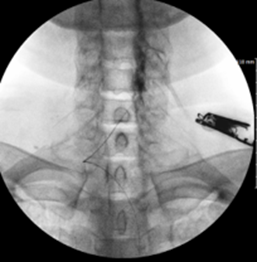

그림3.png 촬영 일시: 2025.04.30

<Fig 1. 경추 4-5, 5-6, 6-7번 세 마디 협착 동반한 디스크>

그랬더니 정말 예상대로...

여러 마디에서 디스크 퇴행이 진행되어 있었고,

3개 마디에서는 척추관 협착증까지 확인됐어요.